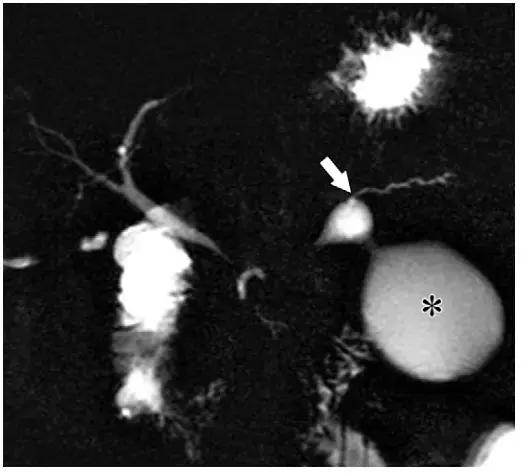

在 MR 成像中,假性囊肿表现为均匀高 T2 信号(图 6)。MRCP 具有高组织分辨率,可以显示部分假性囊肿与胰管相通(图 7)。

低于 10% 的 IEP 患者的假性囊肿会进展。典型假性囊肿位于胰周,极少数情况下,坏死组织清除术后胰管内胰液流入手术部位形成胰腺内假性囊肿。

在这些病例中,坏死组织清除术后或胰体坏死,而胰尾仍有功能,分泌胰液并从胰管内漏出形成假性囊肿(图 7)。